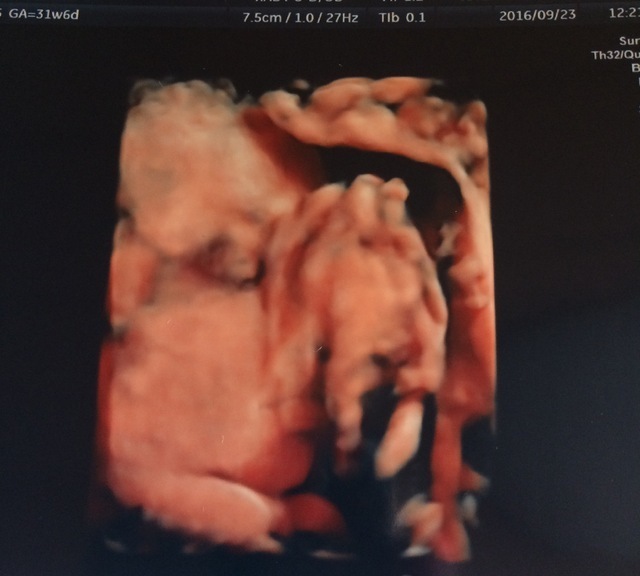

31週1日(31w1d・女の子)|Fatima さん(26歳)

エコー写真撮影時のエピソード:

私の通っていたクリニックでは、20週以降、4Dエコーを撮ってもらえました。毎回うずくまってガッツポーズだったため、性別が確定したのも30週を超えてから。これは、ようやく顔が撮れた時の奇跡の一枚です。鼻と口元が旦那そっくり!